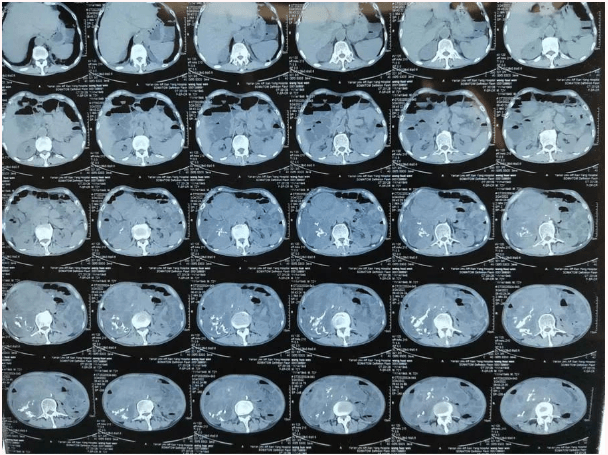

患者王大爷,男,72岁,发现腹腔肿物10余年,近两年来患者双下肢乏力、贫血,依靠间断输血维持着正常生活,出现头昏,行动困难,腹部疼痛及便血慕名来我院就诊。入院后查体评估患者年龄大,体质差,严重贫血,肺部感染及肠梗阻征象,腹部增强CT检查提示腹膜后巨大肿瘤,长径超过30厘米,占据大部分腹腔,并可能存在双原发肿瘤。

苗满园肿瘤外科团队在麻醉科/手术室的紧密配合下为该患者进行手术,术中发现肿瘤巨大,几乎占据了整个腹腔,从左侧向右腹腔延伸,向上将肝、肾挤向膈下,向左将胃及小肠挤向左上腹,向下深达盆腔内,包绕下腔静脉、肠系膜上动脉等大血管及输尿管,回盲部及回肠也受侵犯。手术难度巨大,风险极高。团队凭借着高超的手术技能和精准的手术预案沉着应对,迎难而上,应用高频电刀、超声刀、切割缝合器等先进设备,耗时近5小时为患者切除了巨大腹腔肿瘤,并联合右半结肠切除,术中出血仅50ml。术后病理为腹膜后巨大平滑肌瘤+回肠腺癌。